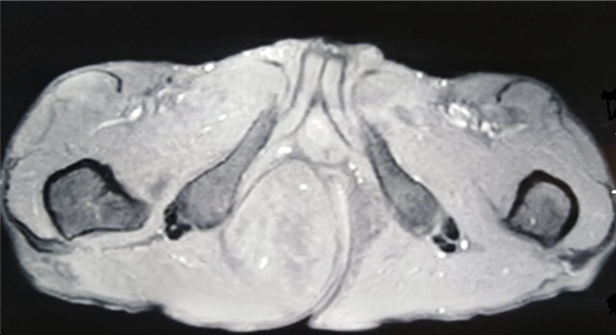

A 69-year-old male patient, consulted with complaints of swelling in the right gluteal region gradually increasing in size for 3 years, with no other associated signs. The clinical examination objected a freely mobile large mass of the right gluteal region measuring 7cmx10cm, soft, non-painful and with no inflammatory signs. There was no history of previous trauma. Magnetic resonance imaging (MRI) revealed a large, well defined mass of the right ischio-rectal pit. It showed high signal on a T2-weighted image (Figure 1), heterogeneous, iso-signal on a T1-weighted image (Figure 2), and a gadolinium-enhanced image (Figure 3), measuring 76-49-108 mm coming into contact with the internal shutter muscle outside, pushing back the anal canal into it without signs of invasion. On the basis of these radiological findings, we suspected a desmoide tumor, or liposarcoma from which the surgical indication was put. The patient was operated on with a single-block excision of the mass without capsular break-in (Figure 4-6). The surgical suites were simple. A histopathological examination revealed a well circumscribed mass composed of a mixture of mature adipocytes and spindle cells in varying proportions surrounded by a clear fibrous capsule. Neither the lipomatous nor the spindle cell elements of the tumors showed evidence of necrosis or mitotic activity. The immune histochemical analysis, showed that the lesional spindle cells were strongly immunoreactive for CD34 and the results of MDM2 immunostaining were negative. The diagnosis of SCL of the gluteal region was concluded.

Figure 3 Axial section of Pelvic MRI showing a mass with gadolinium-enhanced on a T1-weighted image.